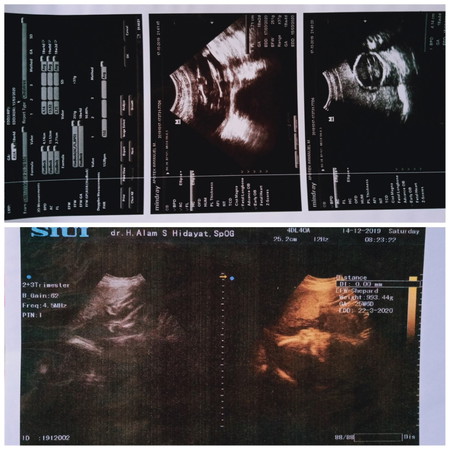

Alhamdulillah, Terimakasih yaAllah telah mempercayakannya tumbuh dan berkebang dg sehat dirahimku menjadikan ini salah satu kado terindah diultahku kali ini ? Terimakasih babyku syank sehat dan kuat terus ya ddlm perut mama, terus kerja sma sampai lahiran nnti ❤️ Untuk bunda2 yg mentikan dan sedang program hamil semoga secepatnya mendapat kabar bahagia ada dedek dlem perut, aamiin ?? . #26week3day #hplMaret #InsyaAllahbabyboy ❣️